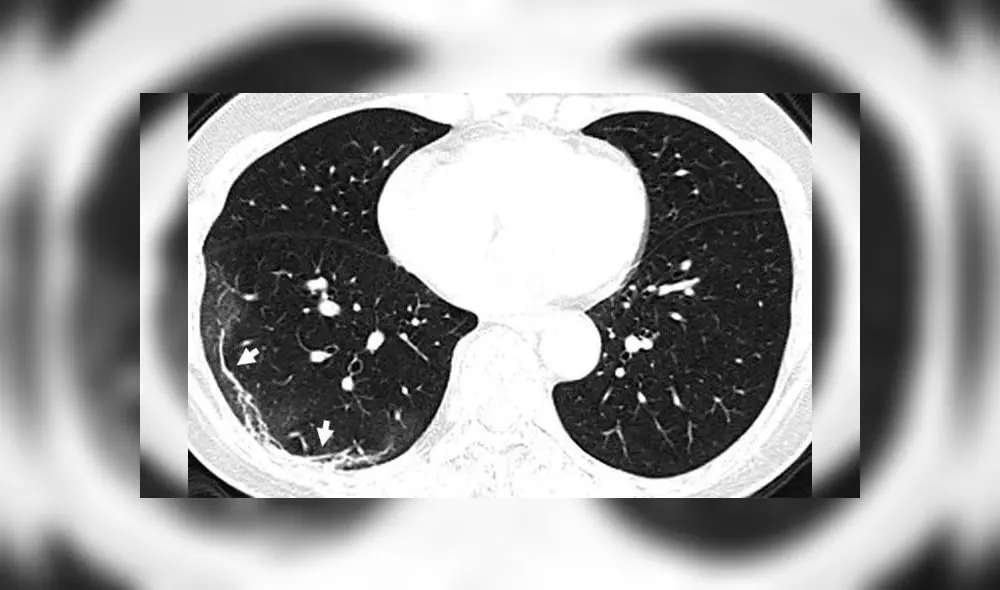

Estas anomalías indican un llenado parcial de espacios de aire en los pulmones, de forma parecida a lo registrado en pacientes con enfermedades como el SARS y el MERS.

Otro conjunto de imágenes computarizadas muestra el mismo llenado de espacios de aire en los pulmones de una mujer de 54 años, quien se infectó con coronavirus tras un viaje a Wuhan. Ella experimentó fatiga, tos, fiebre y congestión en el pecho, siendo luego diagnosticada con neumonía severa ocasionada por el COVID-19.

También se ven manchas blancas en los pulmones de una mujer de 45 años que dio positivo por el virus tras regresar de Japón.